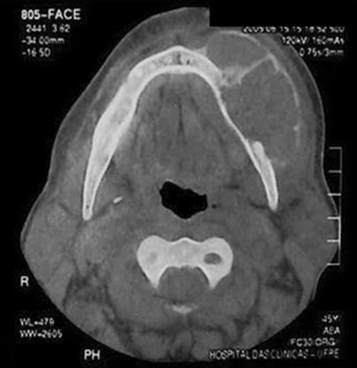

Рис.4: Компьютерная томография: визуализируются образования большеберцовой кости в виде гиподенсных масс, в которых прослеживается кистозная структура

Рис. 5: КТ – признаки бурой опухоли верхней челюсти: гиподенсный литический очаг с расслоением надкостницы